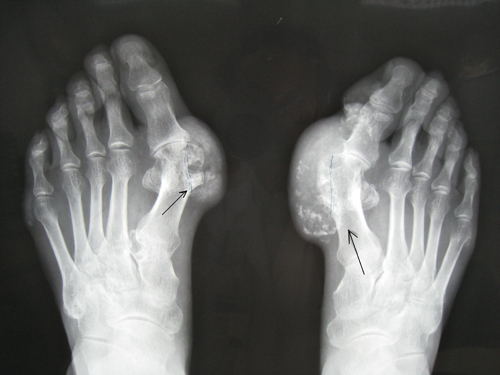

3、慢性期:这个阶段的痛风主要的外在症状体现以慢性关节炎为主,还伴有各种并发症。存在痛风石,慢性关节炎、尿酸结石和痛风性肾炎及并发症。此时痛风频繁发作,身体部位开始出现痛风石,随着时间的延长痛风石逐步变大。相关推荐:老年痛风患者的健康护理